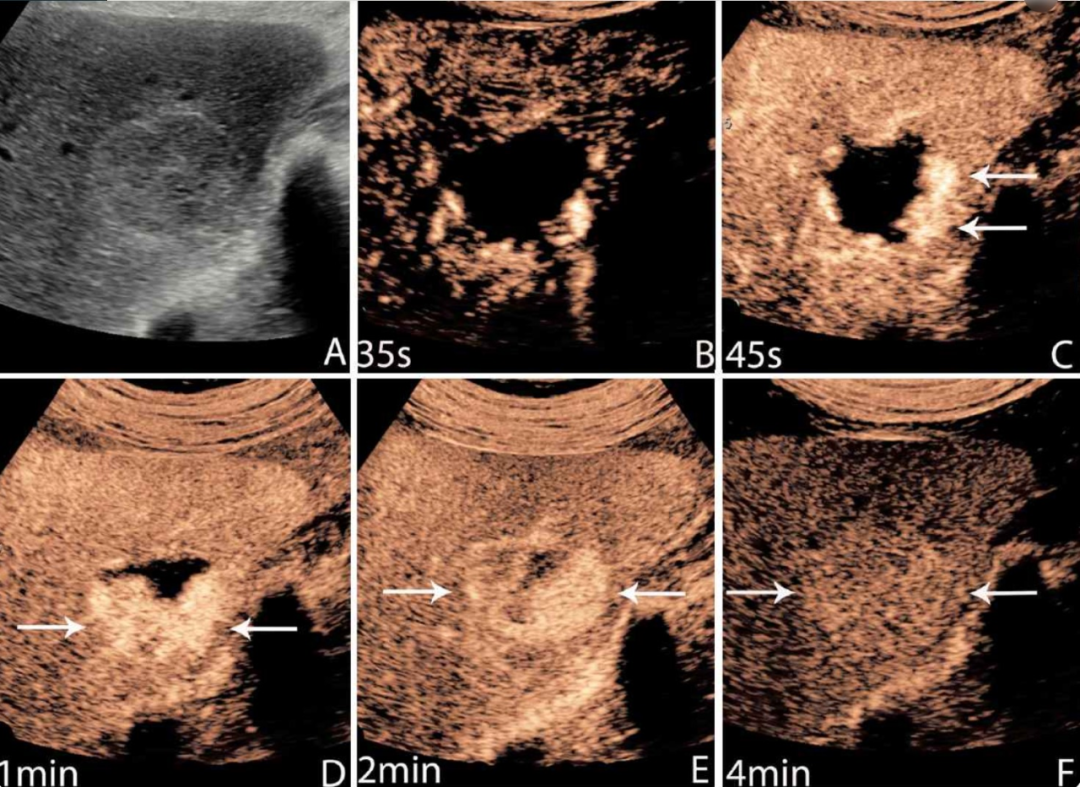

△ 与常规超声相比,肝脏病变的对比增强超声图像显示了不同时间点的动态增强模式

研究显示,超声造影在鉴别肝脏良恶性病变方面的敏感性高达93%,特异性达90%。这一诊断准确率与CT和MRI相当,但具有实时成像、无辐射、成本低廉等独特优势。

△ 对比增强超声图像显示肝脏局灶性病变随时间的动态增强,超声造影剂在肝脏诊断的成像过程